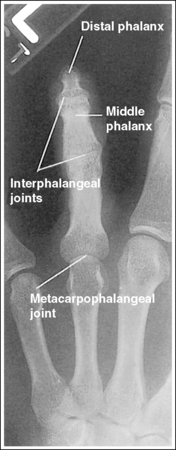

See Figure 4-8 and Box 4-3.

The digit has been placed in a 45-degree PA oblique projection. Twice as much soft tissue width is demonstrated on one side of the digit as on the other side, and more concavity is demonstrated on one aspect of the phalangeal midshafts than on the other.

• A PA oblique finger is accomplished by rotating the affected finger 45 degrees from the PA projection (Figure 4-9). It is most common and comfortable for a patient to rotate the finger and hand externally to obtain a PA oblique finger projection, although internal rotation may be used when the second digit is imaged, to prevent a long object–image receptor distance (OID).

• Assessing accuracy of PA oblique projection. Study the amount of phalangeal midshaft concavity and soft tissue width demonstrated on PA oblique finger projections to verify the accuracy of rotation and to determine the proper repositioning movement needed when an oblique digit image shows too much or too little obliquity. A 45-degree oblique finger image demonstrates more phalangeal midshaft concavity and soft tissue width on the side positioned away from the IR. Use the soft tissue width to assess the degree of digital obliquity. If twice as much soft tissue width is present on one side of the digit as on the other, a 45-degree PA oblique projection has been obtained. If the phalangeal midshaft concavity and soft tissue width on both sides of the finger are more nearly equal, the finger was not rotated enough for the projection (see Image 3). If the soft tissue width on one side of the digit is more than twice as much as that on the other, and when one aspect of the phalangeal midshaft is concave but the other aspect is convex, the angle of obliquity was more than 45 degrees (see Image 4).

Image 3

Image 4

No soft tissue overlap from adjacent digits is present.

• Slightly spread the patient's fingers to prevent overlapping of the adjacent finger's soft tissue onto that of affected finger. Superimposition of these soft tissues makes it difficult to evaluate the soft tissue of the affected finger (see Image 5).

The IP and MP joints are visualized as open spaces, and the phalanges are not foreshortened.

• The IP and MP joint spaces are open and the phalanges are not foreshortened if the finger is fully extended and positioned parallel with the IR and perpendicular to the central ray. When the hand and fingers are positioned obliquely, some of the fingers are no longer placed against the IR but are positioned at varying OIDs. In this position the distal phalanges naturally tilt toward the IR. To keep the affected finger parallel with the IR and to maintain open joint spaces, it may be necessary to place an immobilization device beneath the distal phalanx. This is especially true when the second and third digits are imaged because they are at the greatest OID. It is also necessary to center a perpendicular central ray to the PIP joint to maintain open joint spaces. Failure to position the affected finger parallel with the IR and perpendicular to the central ray foreshortens the phalanges and closes the joint spaces (see Image 6).

Image 6

On both sides of the phalanx the soft tissue width and midshaft concavity are almost equal; the patient's finger was positioned at less than 45 degrees of obliquity for the image.

More than twice as much soft tissue width is present on one side of the phalanges as on the other. One aspect of the midshafts of the phalanges is concave, and the other aspect is slightly convex. Obliquity was more than 45 degrees for this image.

Soft tissue from an adjacent finger is superimposed over the affected finger's soft tissue; the fingers were not spread apart.

Spread the fingers until the adjacent fingers are positioned away from the affected finger.

The IP joint spaces are closed, and the distal and middle phalanges are foreshortened; the finger was not positioned parallel with the IR.

Position the finger parallel with the IR. It may be necessary to position an immobilization device beneath the distal phalanx to maintain accurate finger positioning. If the distal phalanx is of interest and the patient is unable to extend the finger, image it in an AP oblique projection, elevating the proximal metacarpals until the affected phalanx is aligned parallel with the IR and rotated 45 degrees.